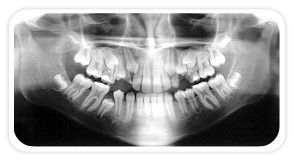

Radiografia mostrando 3º Molares

O último dente a se desenvolver e erupcionar na boca é o 3º molar. Normalmente erupcionam aos 18 anos. Geralmente os 3º molares não tem espaço para erupcionar sendo indicada sua extração, sejam por fins ortodônticos ou profiláticos, para evitar problemas futuros como a reabsorção dos 2º molares, cistos e tumores, entre outros. Estes dentes podem erupcionar parcialmente dificultando a limpeza, acumulando alimentos, placas e bactérias na gengiva sobreposta o que pode resultar em cáries, doenças gengivais, abscessos e infecções não só nos 3º molares como nos dentes vizinhos. Os sisos podem ser extremamente problemáticos, sendo necessária a intervenção de um especialista Buco-Maxilo para sua remoção.